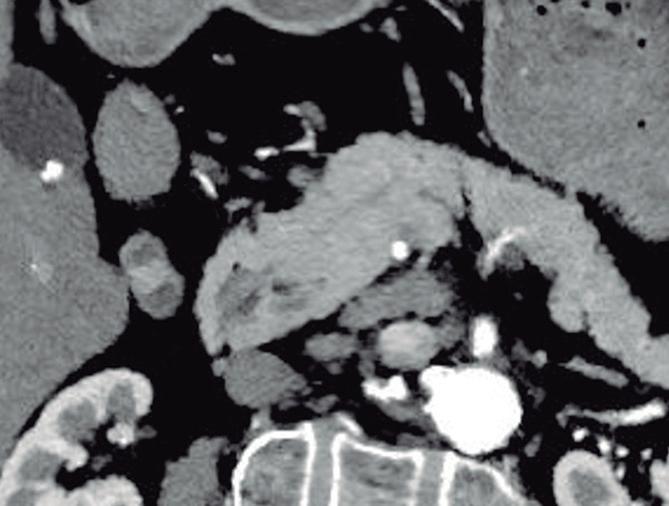

Páncreas Circumportal

El páncreas engloba a la vena mesentérica superior o vena porta, en lugar de rodear al duodeno como sucede en el páncreas anular (Figura 14). Tiene una prevalencia de hasta 2,5% según algunas series, por ende, no es tan infrecuente encontrarlo en estudios por imágenes. Se

A B

postula que su origen está relacionado con una anomalía en la rotación y fusión del brote ventral con el dorsal. Es una condición asintomática, pero cobra relevancia reconocerla e informarla en pacientes que serán sometidos a cirugía del páncreas, con el fin de reducir complicaciones, particularmente la fístula pancreática.25, 26

A) Resonancia magnética, secuencia T1 sin contraste, plano axial. Tejido pancreático con típica señal hiperintensa en secuencia de ponderación tisular T1 (cabezas de flecha), rodeando a la vena porta (VP). B) Resonancia magnética, secuencia T1 con contraste, fase portal, plano axial. VP: vena porta, VE: vena esplénica, AMS: arteria mesentérica superior.